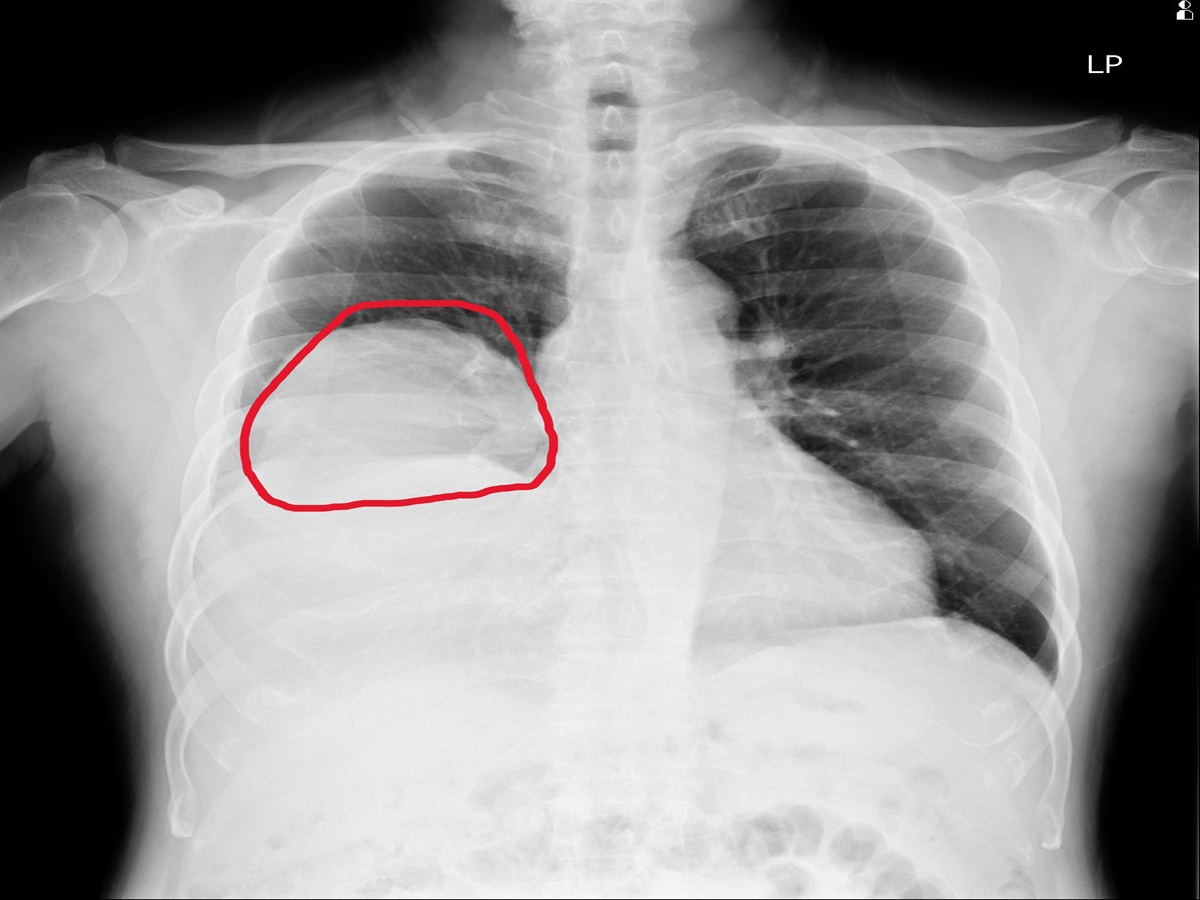

▲經員榮醫療體系醫療團隊深入檢查後,竟發現右肺藏有巨大腫瘤,最終確診為罕見的腫瘤相關低血糖案例。(圖/員榮醫院提供)

住院期間,患者仍頻繁出現低血糖發作,甚至血糖多次低於30 mg/dL,需持續補充高濃度葡萄糖維持穩定。進一步透過胸部X光與電腦斷層檢查,發現右肺有一顆巨大腫瘤,影像顯示約15×11公分,且壓迫周邊結構,並伴隨肋膜積液與淋巴結腫大情形。

▲經進一步透過胸部X光與電腦斷層檢查,發現右肺有一顆巨大腫瘤,影像顯示約15×11公分。(圖/員榮醫院提供)